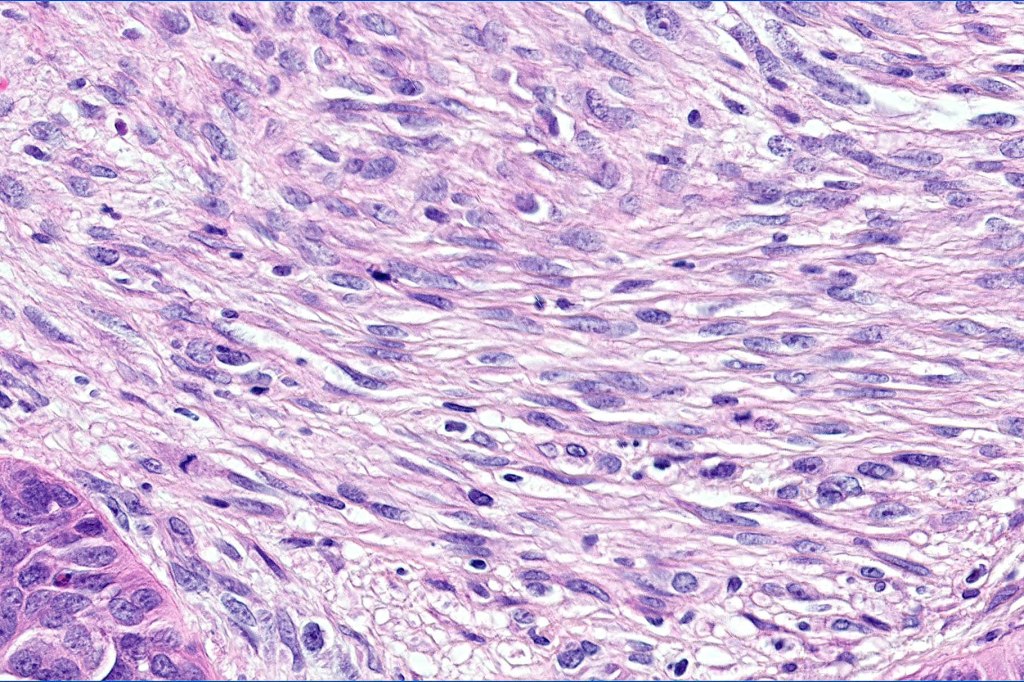

•Trichoblastic sarcoma is characterized by readily recognizable trichoblastoma associated with a high grade sarcomatous element

•Trichoblastic carcinosarcoma combines trichoblastic carcinoma & sarcoma